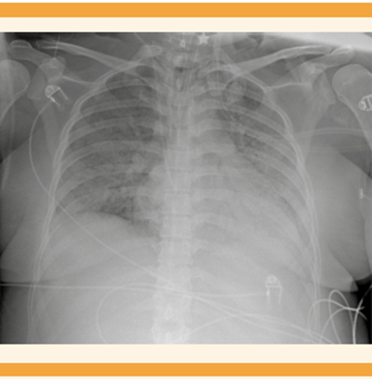

Continuó con deterioro ventilatorio y con saturación de oxígeno al 37%. Al colocarla en posición prona se consiguió que la saturación de oxígeno llegará al 83%, la gasometría con acidosis respiratoria (pH de 7.18, pCO2 61.9 mmHg, pO2 59.9 mmHg, HCO3 23.8 mEq/L); proteína C reactiva (PCR) 14.2 mg/dL, ferritina 237 ng/mL, leucocitos 9.7 x 103, hemoglobina de 12.3 g/dL, plaquetas 274 x 103 y glucosa 225 mg/dL. El cultivo de secreción bronquial reportó Klebsiela pneumoniae BLEE y el hemocultivo central Enterococcus faeclum. La evaluación con la escala SOFA obstétrica (Sequential Organ Failure Assessment) reportó 8 puntos, APACHE II-M (Acute Physiology and Chronic Health Evaluation II Modificado) con mortalidad estimada en 25%. Se integraron los diagnósticos de choque séptico de origen pulmonar, síndrome de insuficiencia respiratoria aguda severo, neumonía viral por SARS-CoV-2, insuficiencia respiratoria mixta con hipoxemia grave y acidosis respiratoria severa. Se indicó tratamiento con: fluconazol, meropenem, linezolid, heparina de bajo peso molecular y prednisona. Dos días después se logró regresar a la posición supina con saturación de oxígeno al 98%. Gradualmente se retiró el vasopresor y la sedación. Figuras 1y2

Figura 1 Radiografía de tórax AP. En el lado izquierdo se observa un patrón de vidrio despulido generalizado con borramiento de los ángulos cardiofrénicos y costodiafragmáticos, índice cardiotorácico de 0.6.